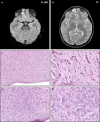

Neurofibromatosis type II (NF2) is a tumor predisposition syndrome characterized by the development of distinctive nervous system lesions. NF2 results from loss-of-function alterations in the NF2 gene on chromosome 22, with resultant dysfunction of its protein product merlin. NF2 is most commonly associated with the development of bilateral vestibular schwannomas; however, patients also have a predisposition to development of other tumors including meningiomas, ependymomas, and peripheral, spinal, and cranial nerve schwannomas. Patients may also develop other characteristic manifestations such as ocular lesions, neuropathies, meningioangiomatosis, and glial hamartia. NF2 has a highly variable clinical course, with some patients exhibiting a severe phenotype and development of multiple tumors at an early age, while others may be nearly asymptomatic throughout their lifetime. Despite the high morbidity associated with NF2 in severe cases, management of NF2-associated lesions primarily consists of surgical resection and treatment of symptoms, and there are currently no FDA-approved systemic therapies that address the underlying biology of the syndrome. Refinements to the diagnostic criteria of NF2 have been proposed over time due to increasing understanding of clinical and molecular data. Large-population studies have demonstrated that some features such as the development of gliomas and neurofibromas, currently included as diagnostic criteria, may require further clarification and modification. Meanwhile, burgeoning insights into the molecular biology of NF2 have shed light on the etiology and highly variable severity of the disease and suggested numerous putative molecular targets for therapeutic intervention. Here, we review the clinicopathologic features of NF2, current understanding of the molecular biology of NF2, particularly with regard to central nervous system lesions, ongoing therapeutic studies, and avenues for further research.